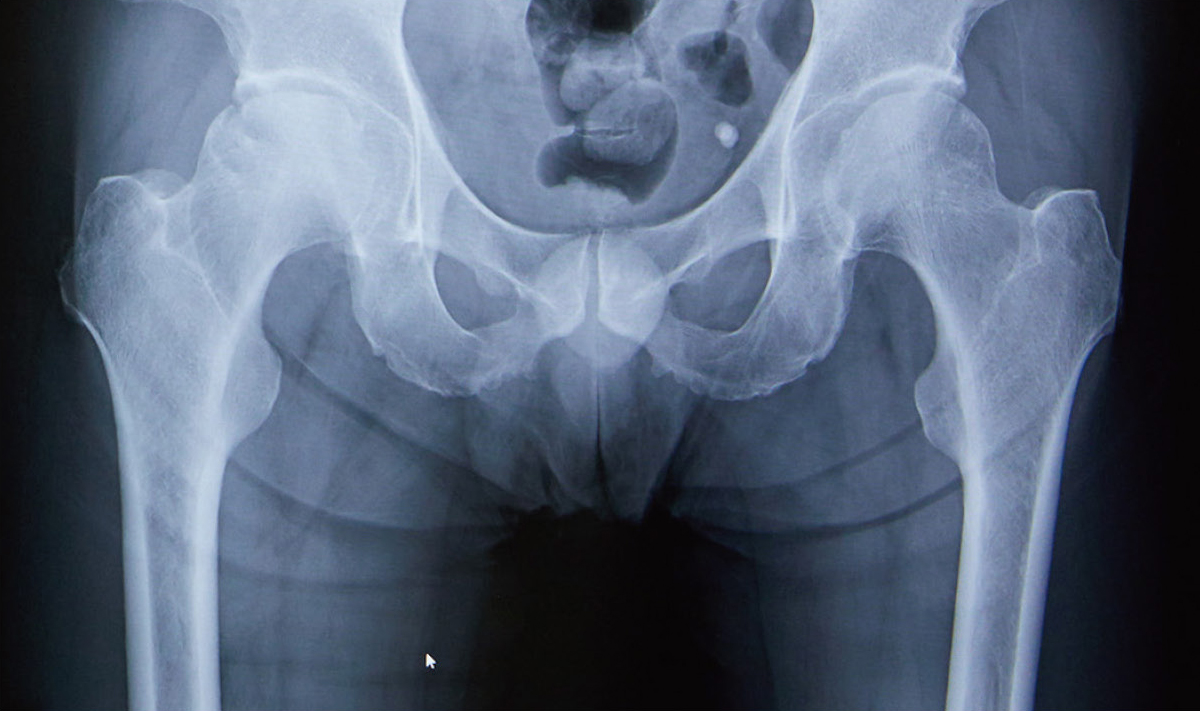

骨盤のX線写真

現在、特定の目的に応じてさまざまな種類の X 線が利用可能です。骨盤の X 線写真は、生殖器や消化器官の多くが存在する腰の間の領域に特に焦点を当てます。骨盤は腸骨、坐骨、恥骨という 3 つの骨で構成され、股関節も形成されます。